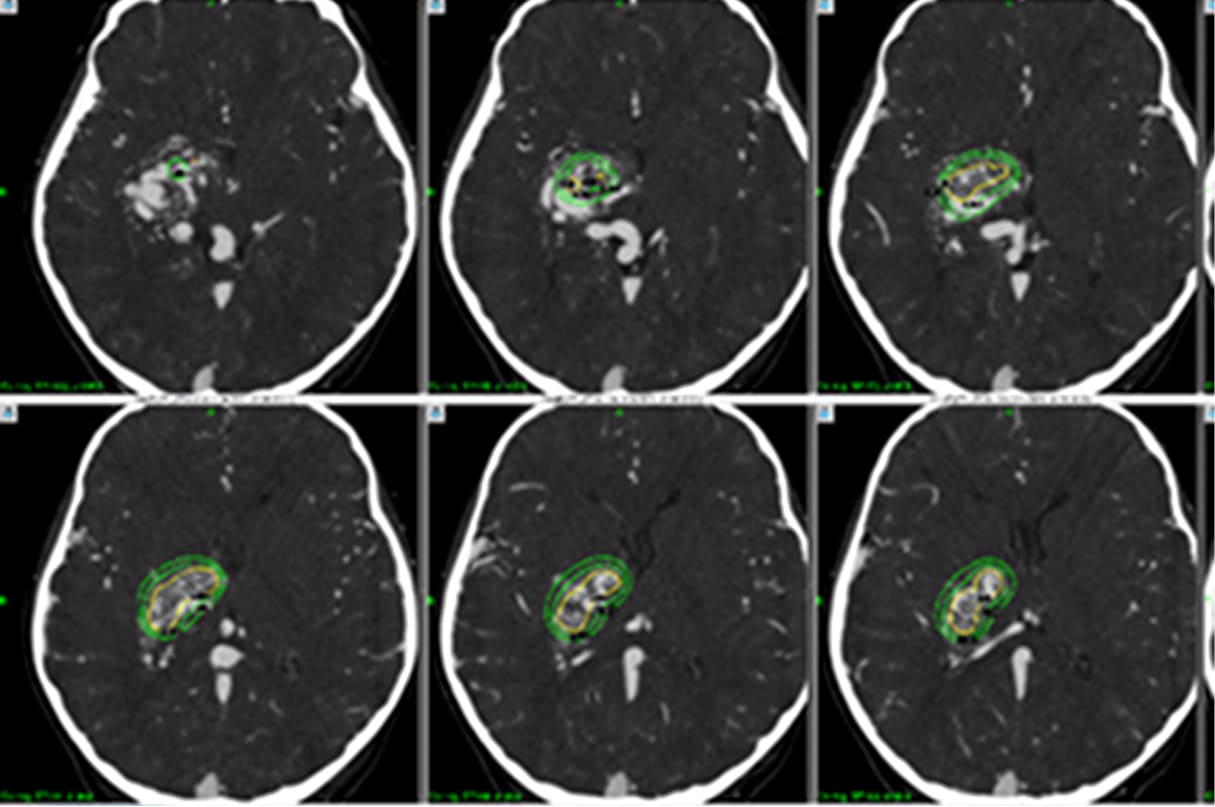

ブレインラボ・エレメンツ

における治療ターゲッテイング

データインストール後の

ガンマプランにおける治療計画